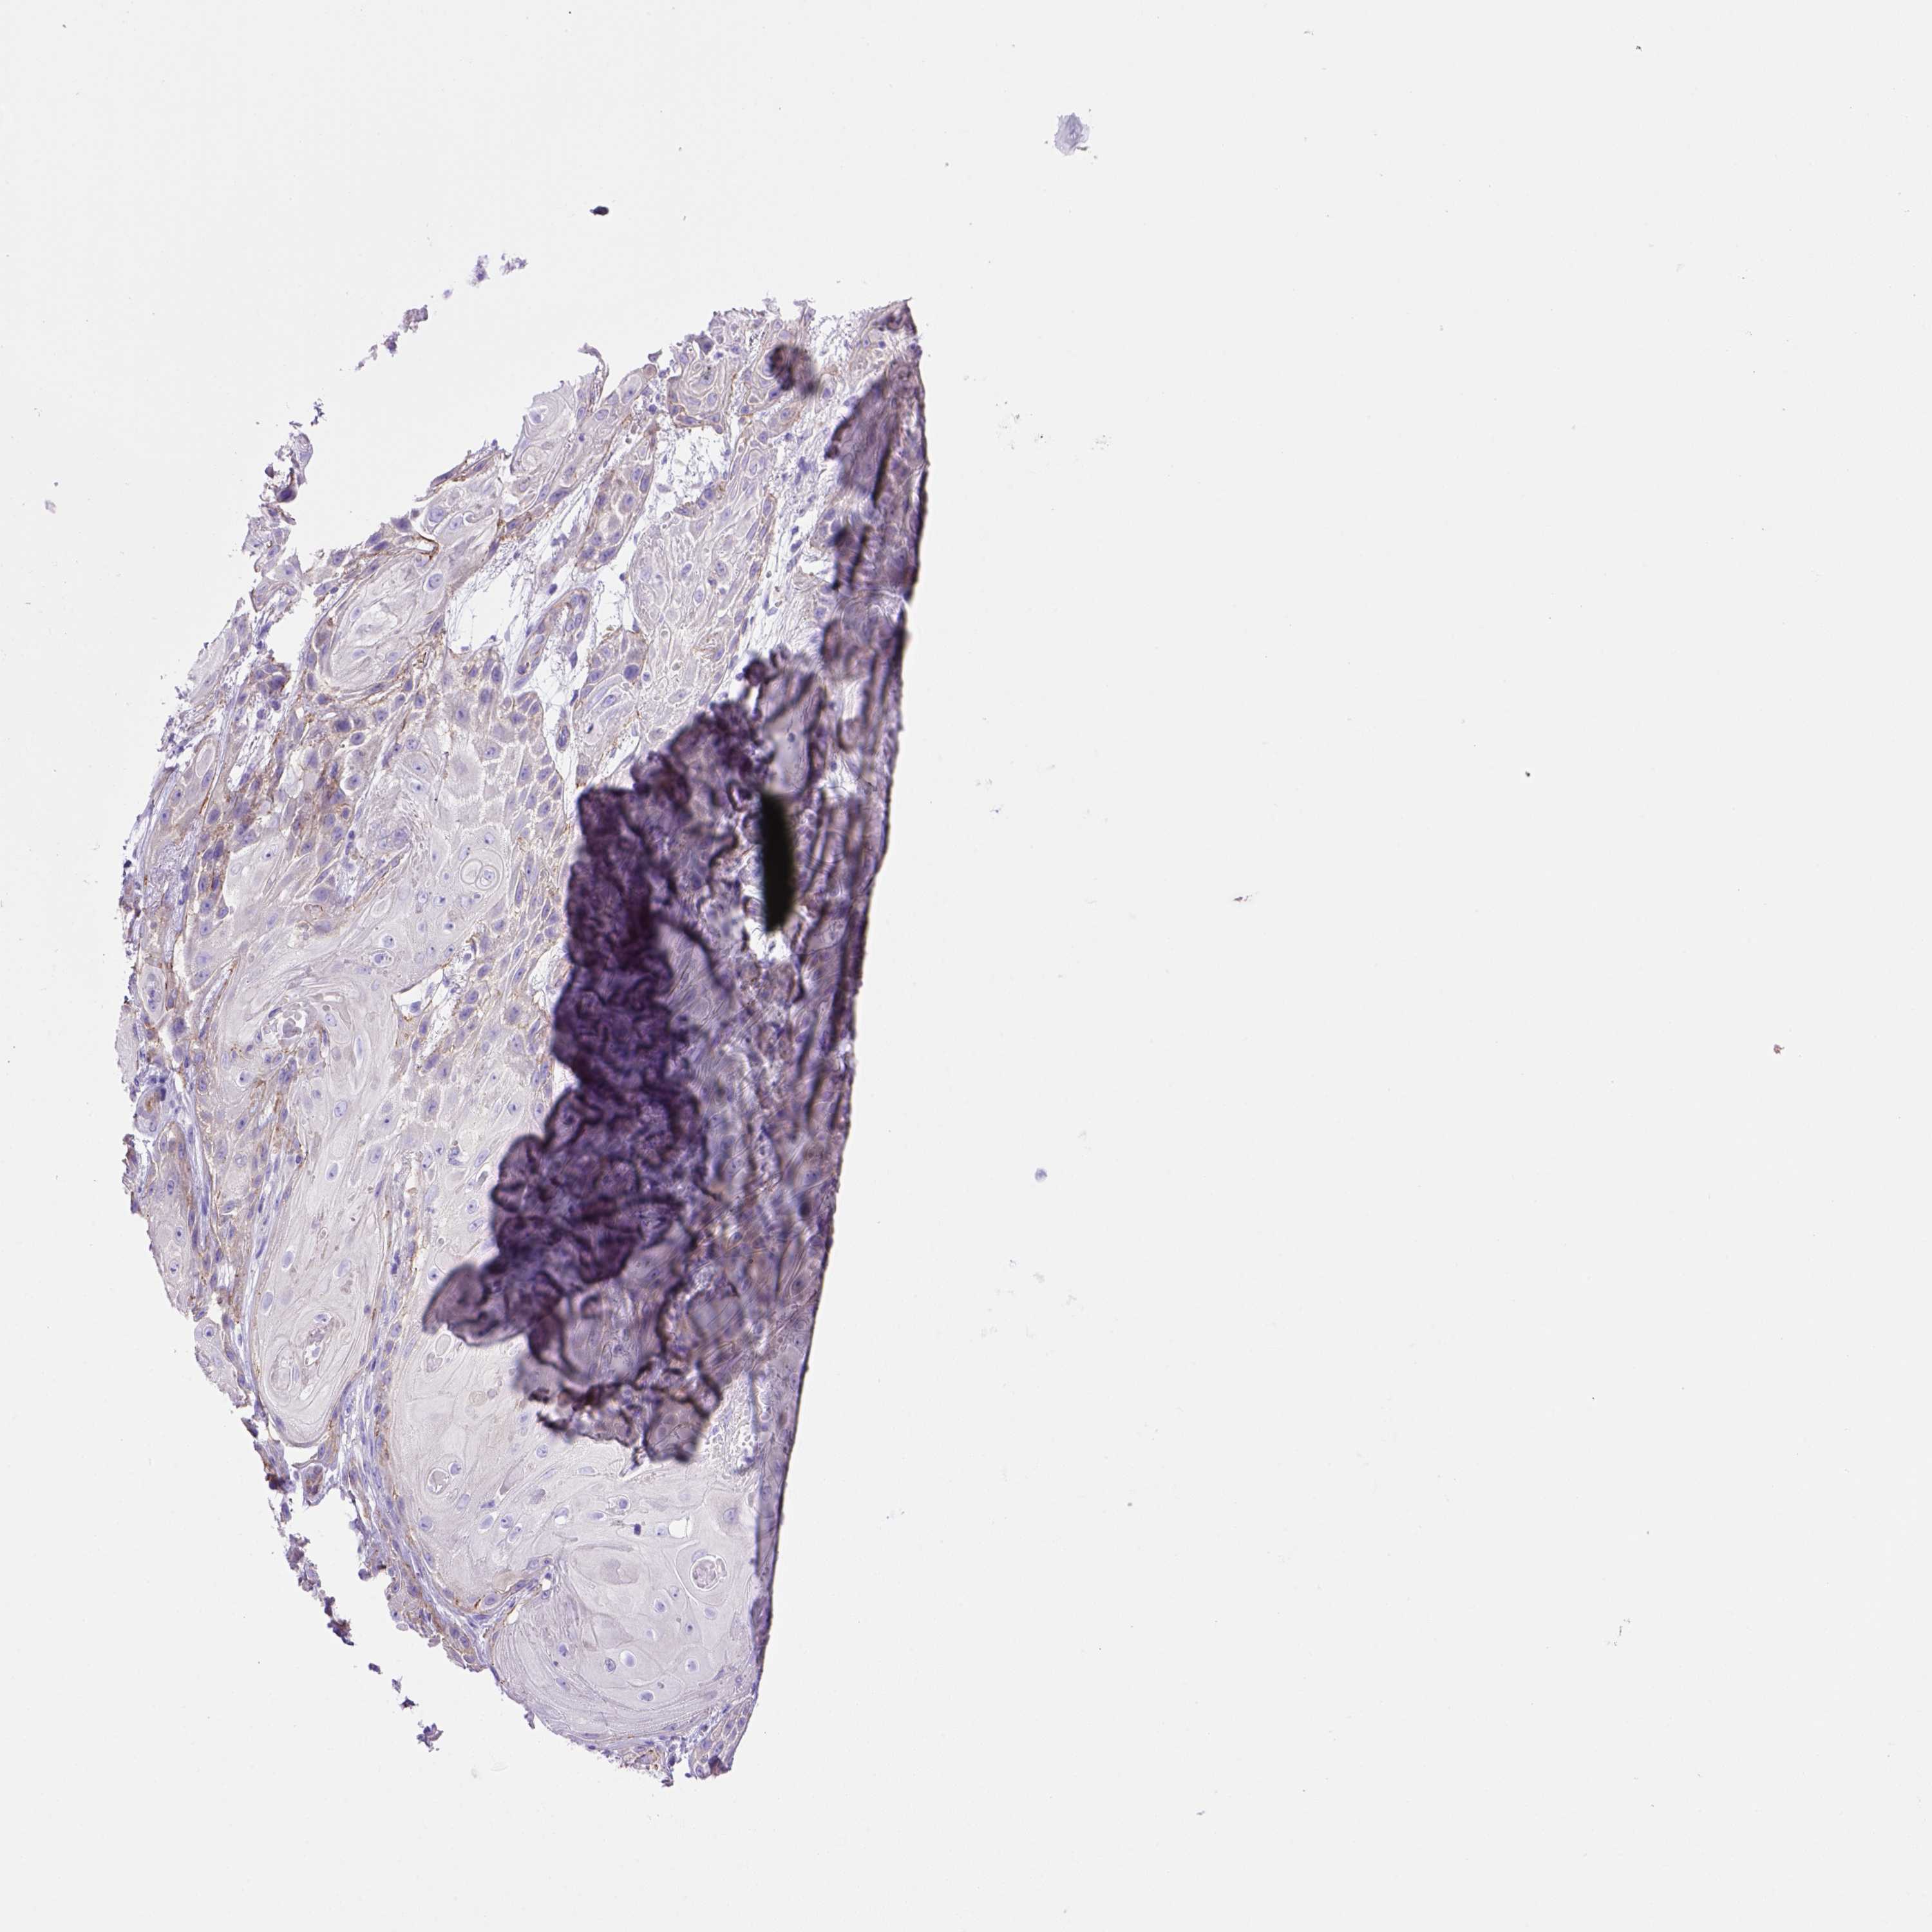

Basal cell and squamous cell cancer

SKIN CANCER - Protein expressioni

A mouse-over function shows sample information and annotation data. Click on an image to view it in a full screen mode. Samples can be filtered based on level of antibody staining by selecting one or several of the following categories: high, medium, low and not detected. The assay and annotation is described here.

Antibody stainingi

Antibody staining in the annotated cell types in the current human tissue is reported as not detected, low, medium, or high, based on conventional immunohistochemistry profiling in selected tissues. This score is based on the combination of the staining intensity and fraction of stained cells.

Each image is clickable and will lead to virtual microscopy that enables deeper exploration of all samples and also displays staining intensity scores, fraction scores and subcellular localization as well as patient and tissue information for each sample.

Antibody HPA069386

Staining

High

Medium

Low

Not detected

Intensity

Strong

Moderate

Weak

Negative

Quantity

>75%

75%-25%

<25%

None

Location

Nuclear

Cytoplasmic/membranous

Cytoplasmic/membranous,nuclear

Basal cell carcinoma

Squamous cell carcinoma, NOS